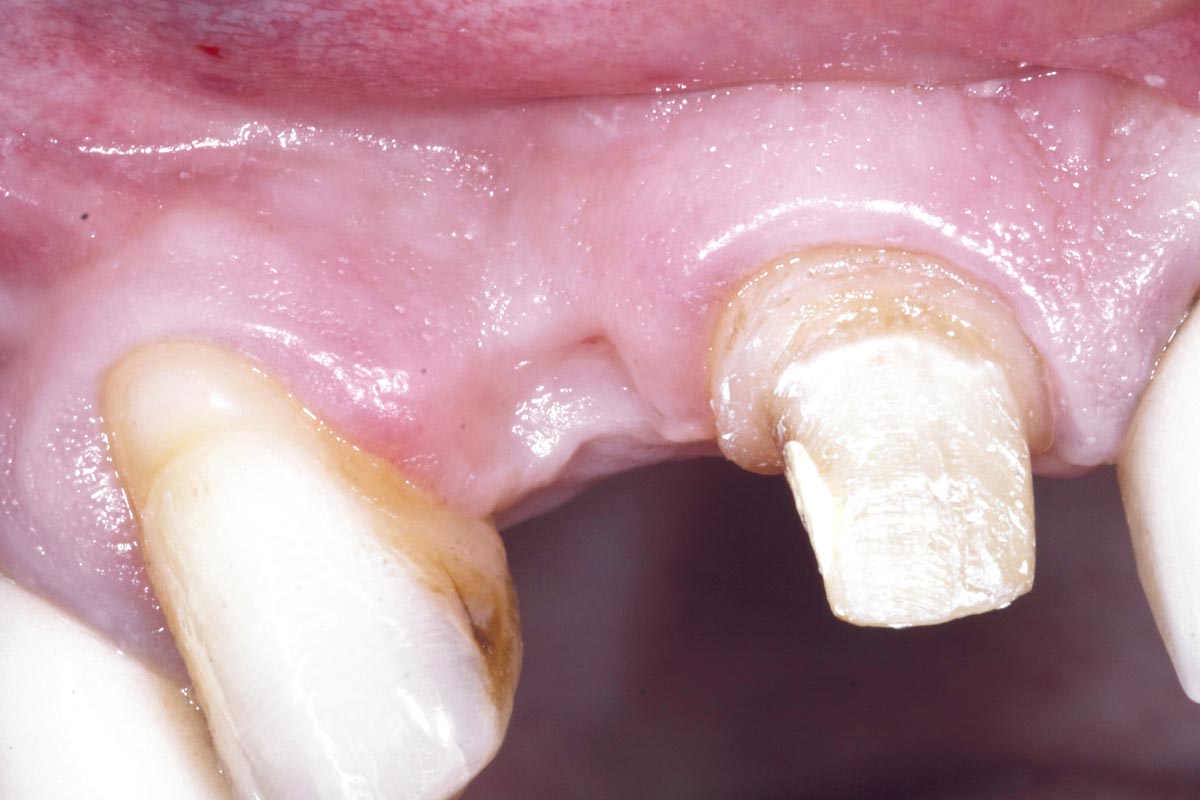

14/19 - Scanning the Implant fixture in situ with Digital Itero Scan including repreparation of adjacent teethBone augementation with maxresorb® - Dr. R. Cutts